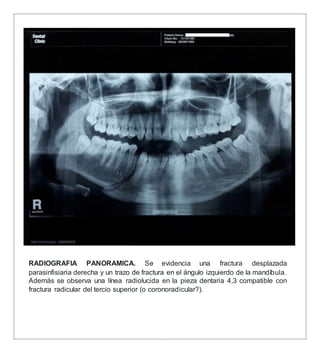

RADIOGRAFIA PANORAMICA. Se evidencia una fractura desplazada

parasinfisiaria derecha y un trazo de fractura en el ángulo izquierdo de la mandíbula.

Además se observa una línea radiolucida en la pieza dentaria 4,3 compatible con

fractura radicular del tercio superior (o coronoradicular?).